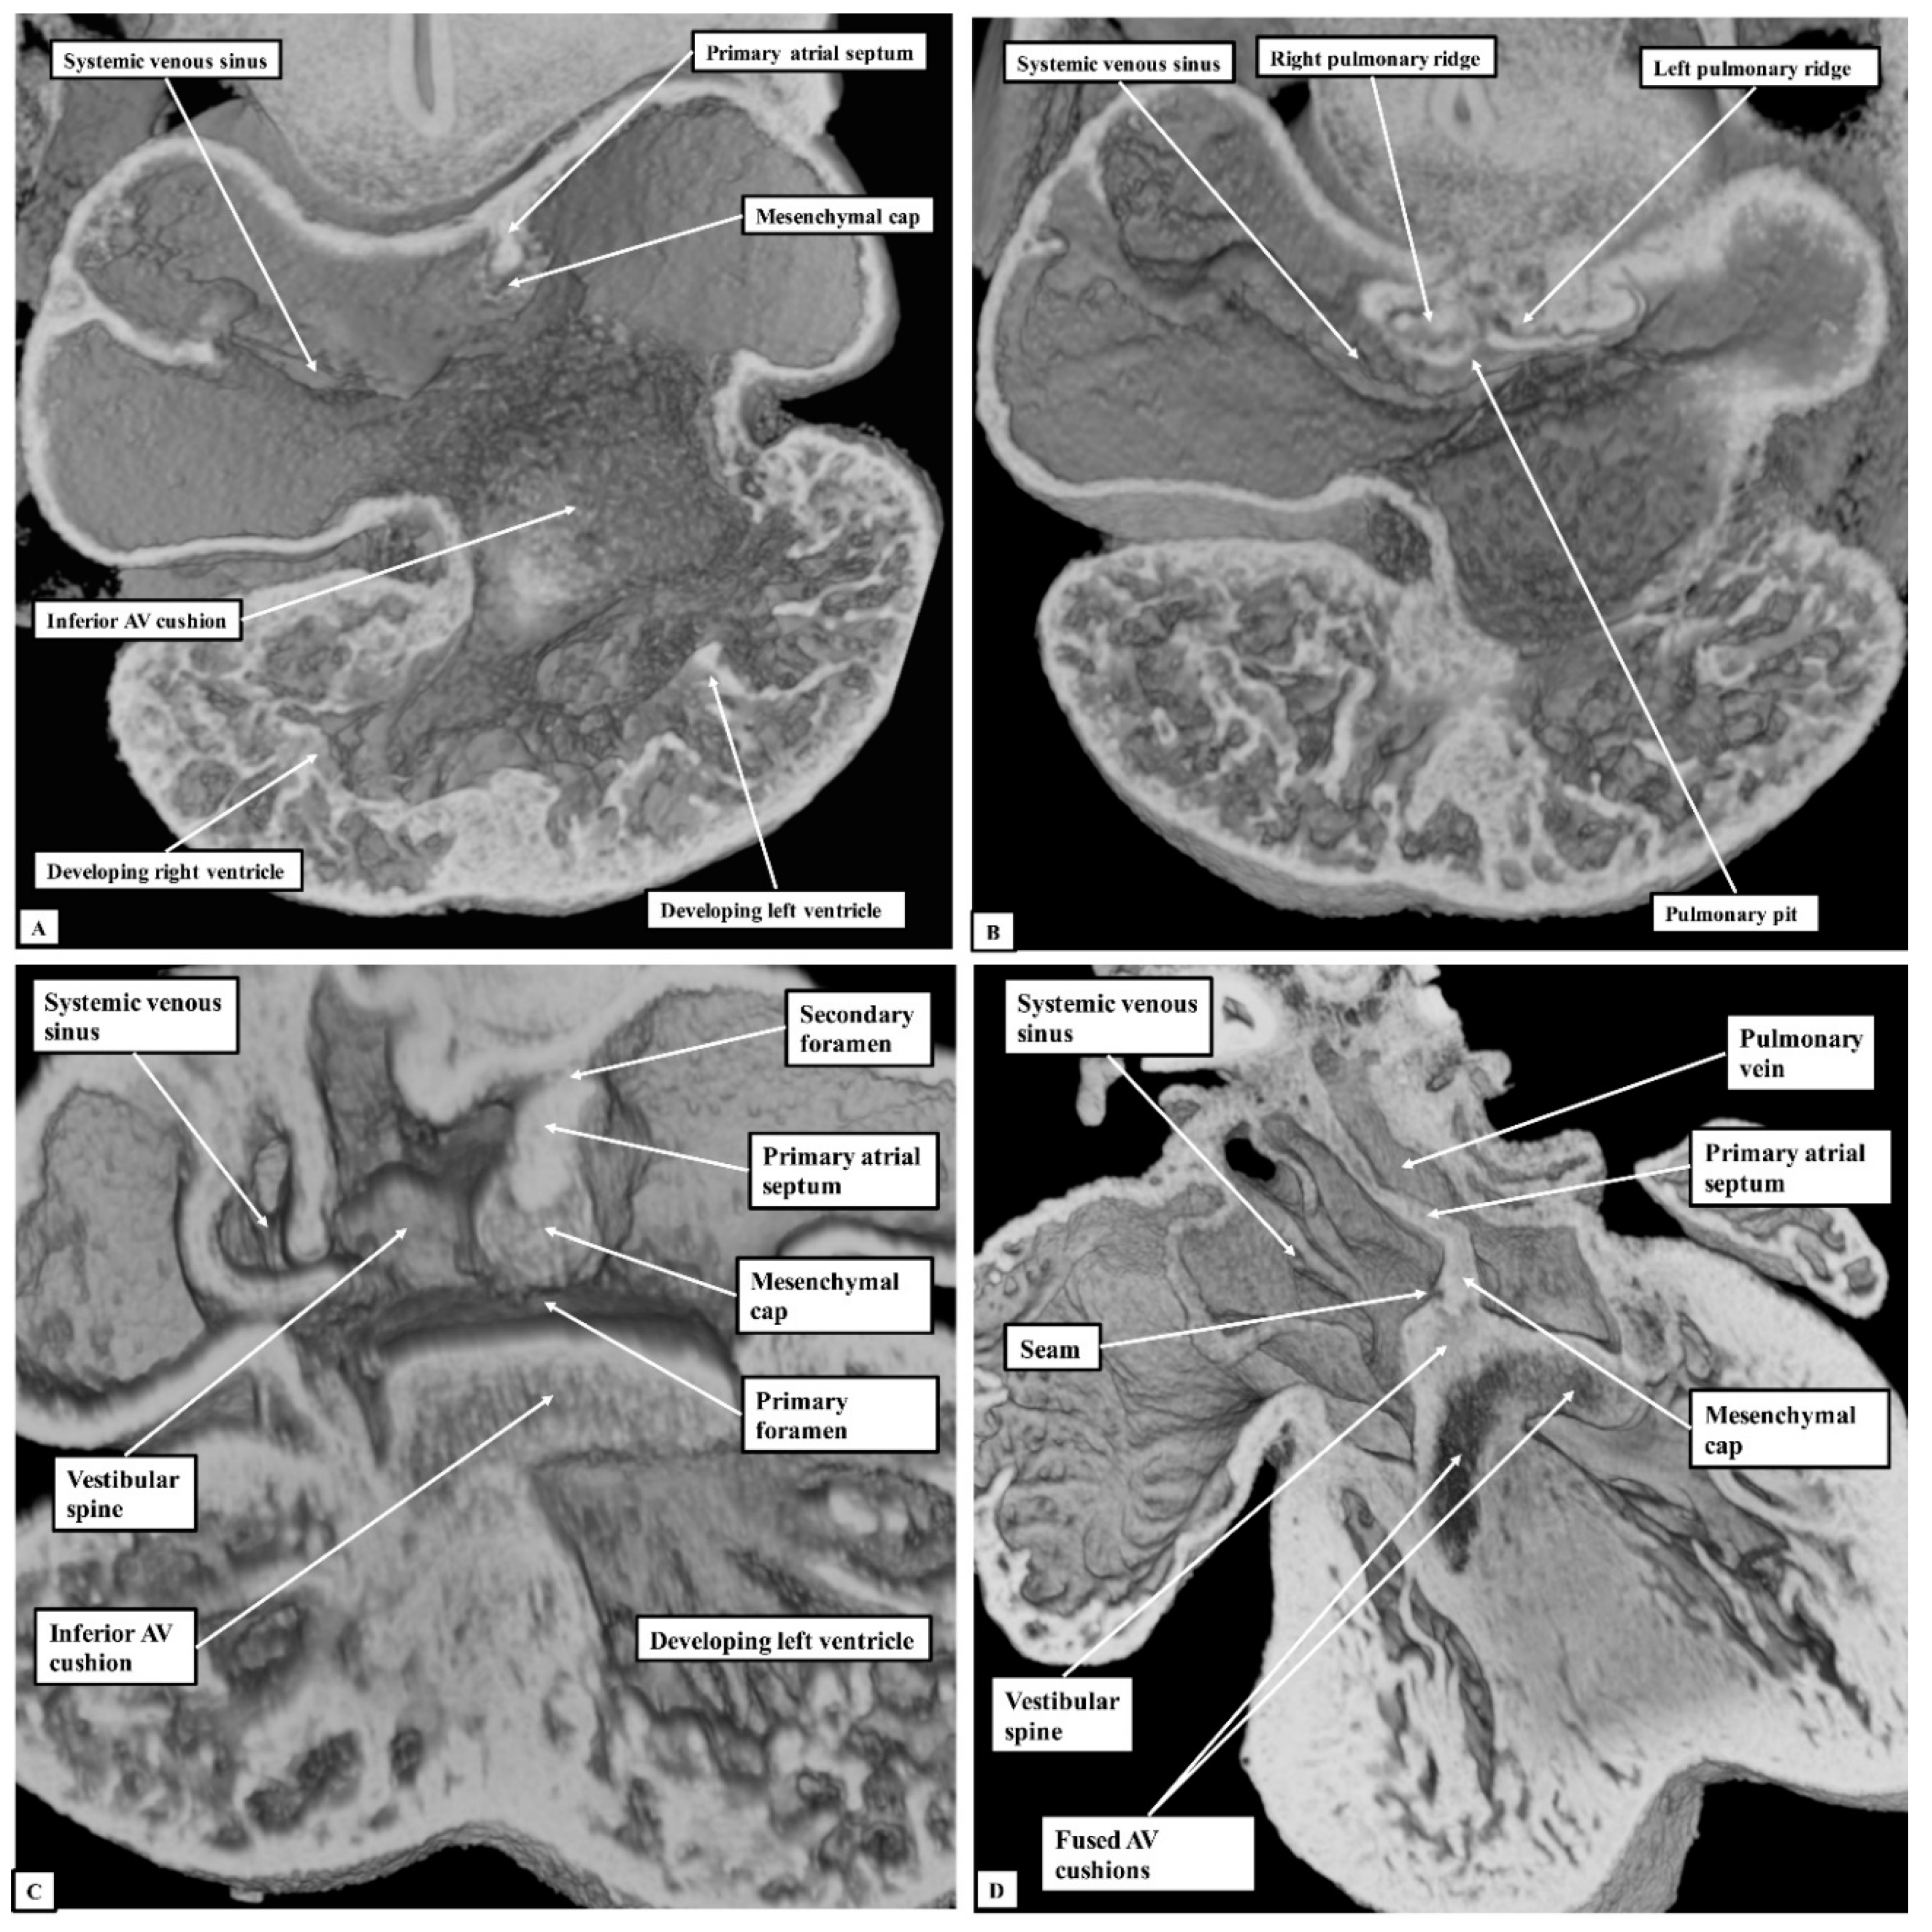

At E10.5, the primary atrial septum can be recognised as a muscular ridge growing from the roof of the atrial component of the heart tube, which is a common structure at this stage of development. By this stage, the borders of the confluence of the systemic venous tributaries with the common atrial cavity are already marked by the venous valves, with the opening of the systemic venous sinus already committed to the right side of the developing atrial chamber (Figure 5A). The atrioventricular canal at this early stage is committed exclusively to the cavity of the developing left ventricle, although the parietal wall of the right atrium is already in continuity with the wall of the developing right ventricle in the roof of the embryonic interventricular communication. The primary septum itself carries a mesenchymal cap on its leading edge, with the space between the cap and the atrioventricular cushions representing the primary atrial foramen. Dorsally at this stage, the atrial walls are continuous with the pharyngeal mesenchyme through the persisting mesocardial connection. Growth from the mesenchyme into the right margin of the mesocardium has already produced inequality in size of its rims, which now protrude into the atrial cavity as the pulmonary ridges (Figure 5B). As yet, there is no formation of the pulmonary veins, but the floor of the dorsal mesocardial connection, known as the pulmonary pit, will eventually provide the site of connection between the developing pulmonary veins and the atrial cavity.

By the next day of intrauterine development (E11.5—Figure 5C), the primary atrial septum has grown towards the cushions developed within the atrioventricular canal. The canal itself has now expanded rightwards so as to bring the cavity of the right atrium into direct connection with that of the right ventricle. The upper margin of the primary foramen has now broken away from the atrial roof to form the secondary atrial foramen, while the size of the primary foramen is much reduced. By now, the growth of mesenchymal tissue into the rightward margin of the dorsal mesocardial connection has produced an intraluminal swelling that overlaps the rightward and dorsal extent of the leading edge of the primary atrial septum. This is the vestibular spine, also known as the dorsal mesenchymal protrusion. The pulmonary vein by this stage has canalised within the pharyngeal mesenchyme, opening to the atrium through the pulmonary pit. The growth of the vestibular spine ensures that the pulmonary venous orifice is committed to the developing left atrium. By E13.5, the mesenchymal cap on the atrial septum has fused with the atrial margins of the atrioventricular cushions, which themselves have fused together to separate the atrioventricular canal into the developing tricuspid and mitral valvar orifices (Figure 5D—Lower right-hand panel). The rightward margin of the cap is now itself overlapped by the vestibular spine, with an obvious seam noted between these structures. The two entities together form the caudal rim of the developing oval fossa. Both by now are losing their mesenchymal characteristics and are attaining the same texture of the walls of the cardiac chambers, which we interpret as indicating their muscularisation. The cranial margin of the fossa can now be recognised as a small ridge formed to the right side of the cranial attachment of the primary atrial septum.

Figure 5. The images show ventral (Panel A) and more dorsal (Panel B) sections taken from the same episcopic dataset prepared from a developing mouse embryo sacrificed on the eleventh day of intrauterine development (E10.5). The lower panels show similar four-chamber sections at the stages of embryonic days 11.5 (Panel C) and 13.5 (Panel D) Abbreviation: AV—Atrioventricular.